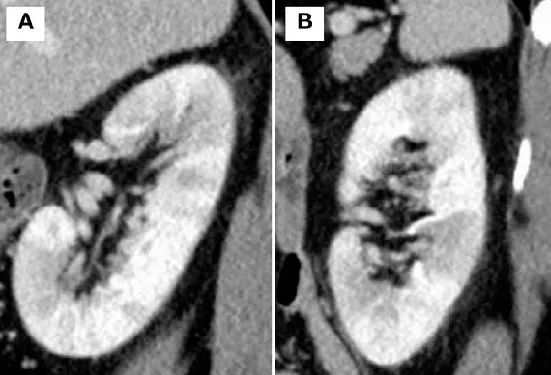

Uma tomografia computadorizada (TC) contrastada revelou focos corticais hipoatenuantes mal definidos e um aumento do volume renal (imagem abaixo).

2. A TC com contraste pode revelar áreas de baixa densidade nos rins